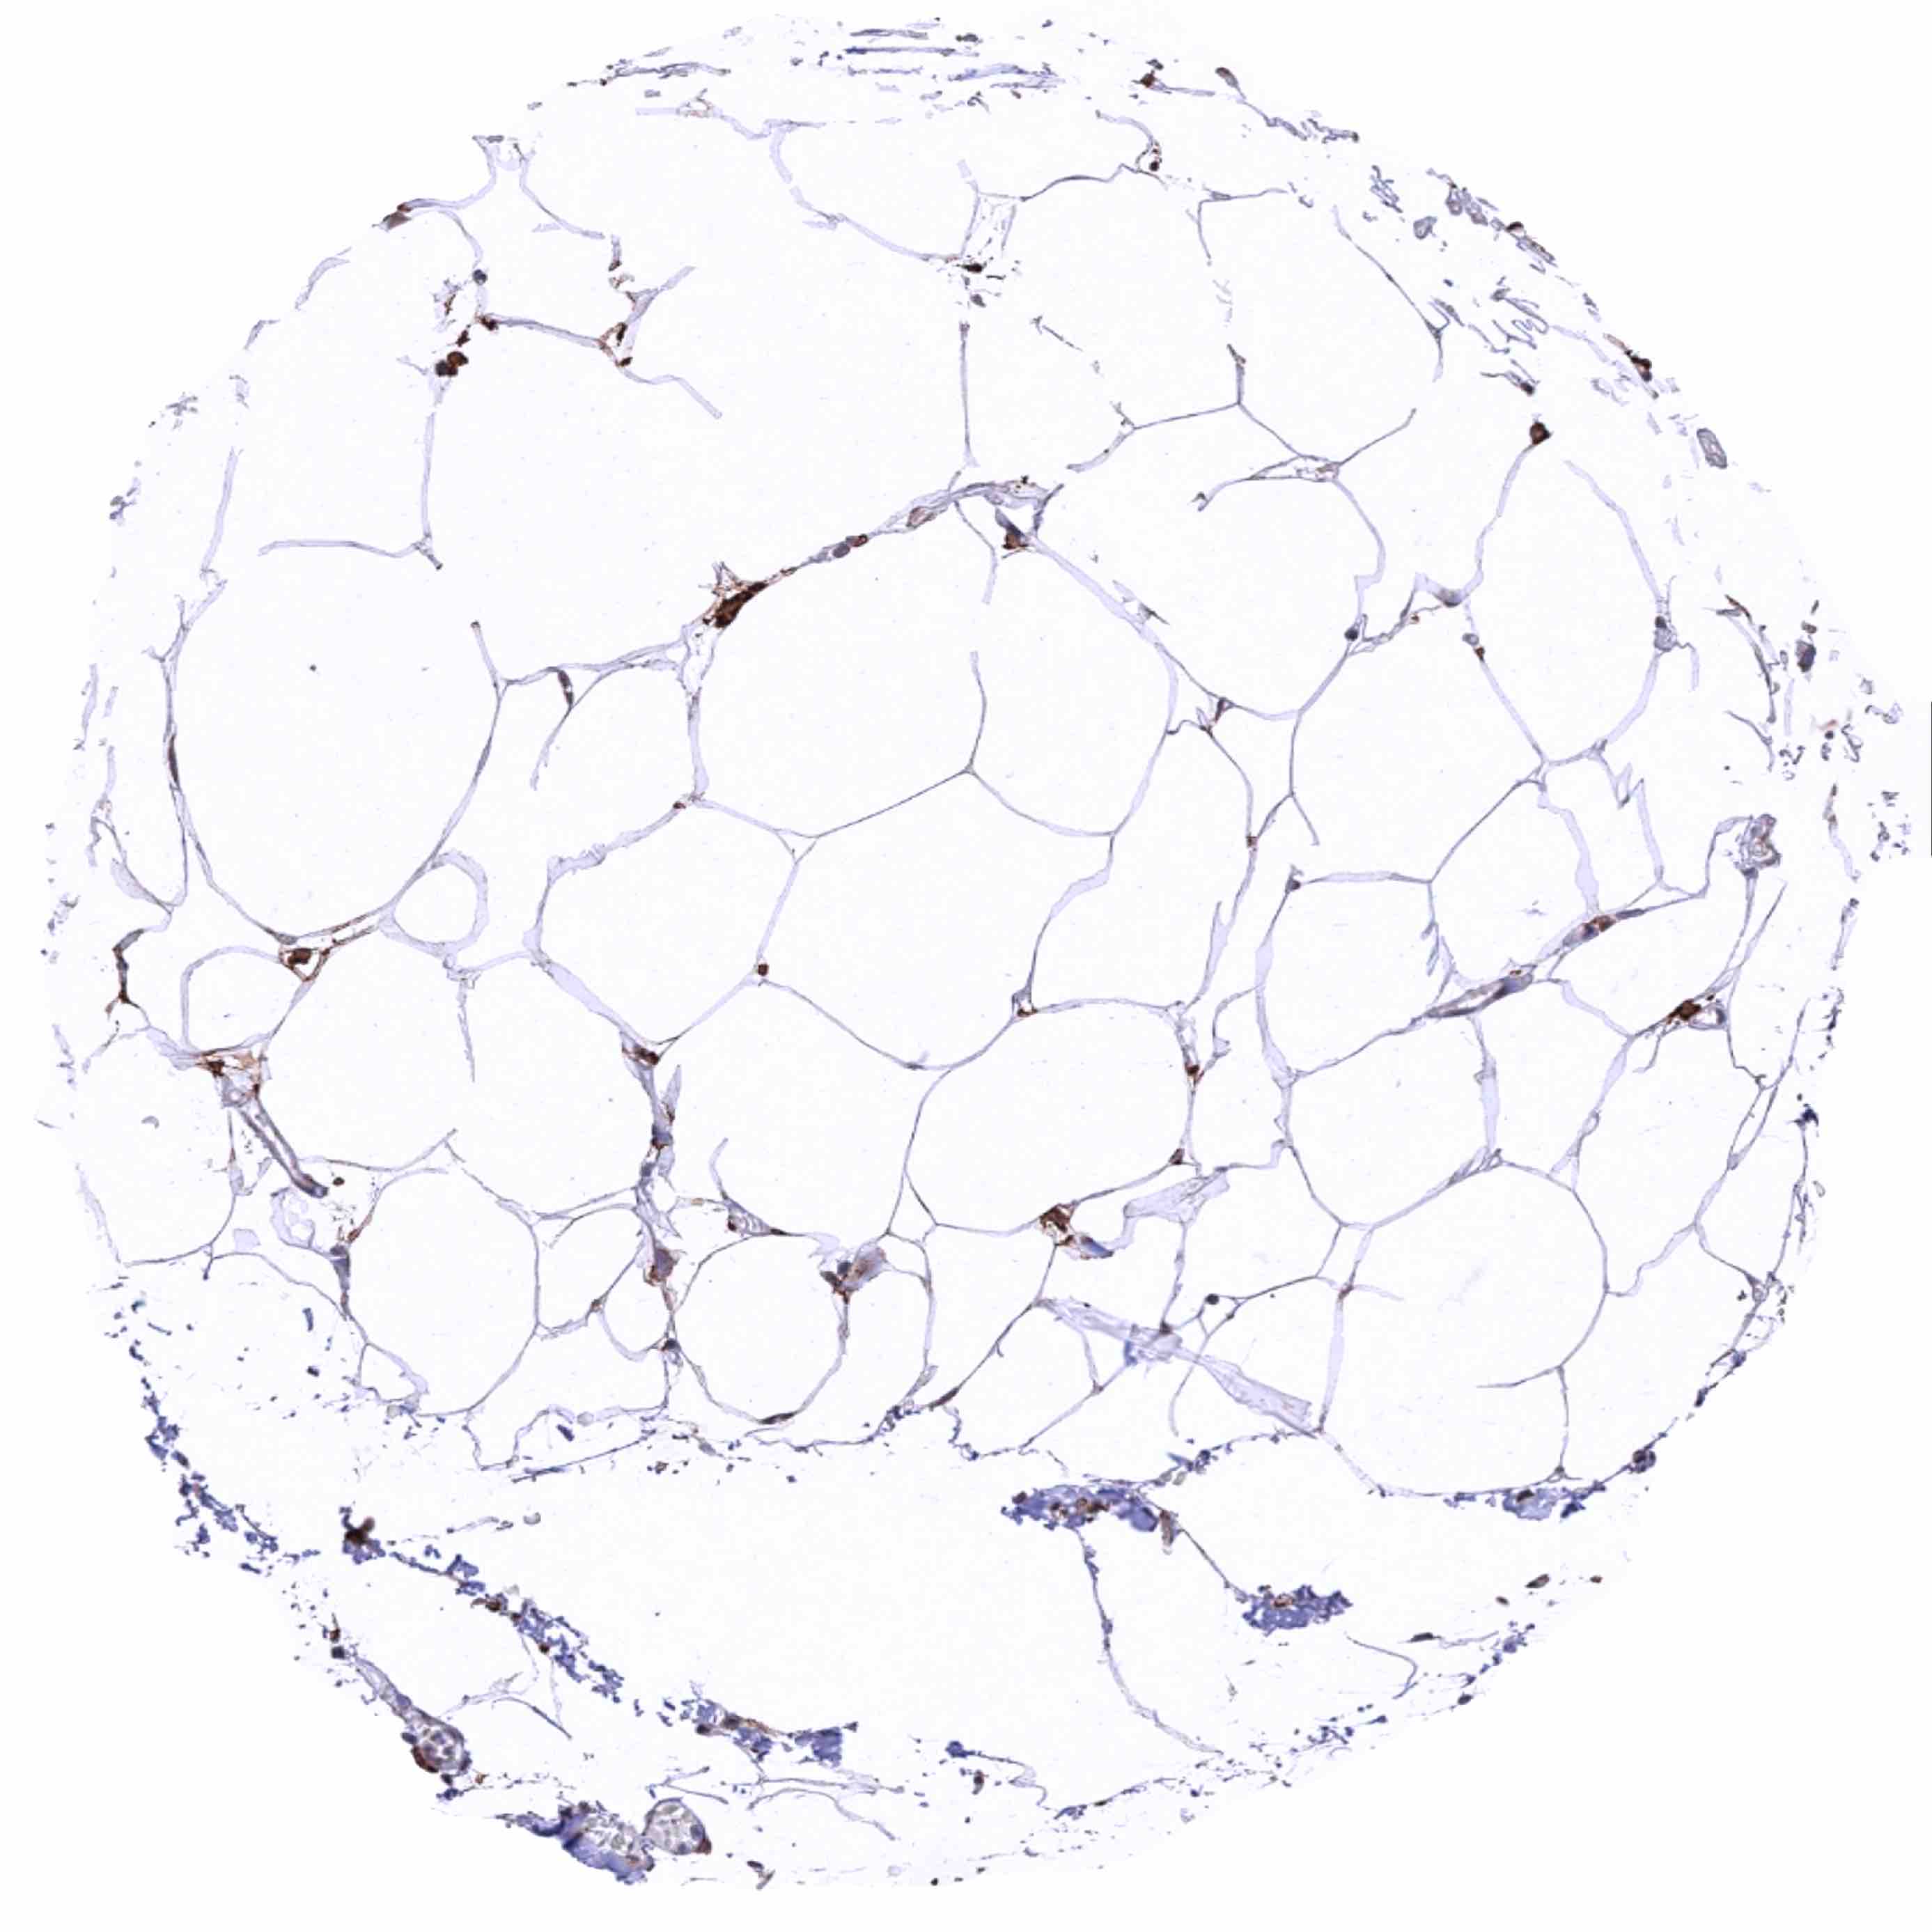

Fat